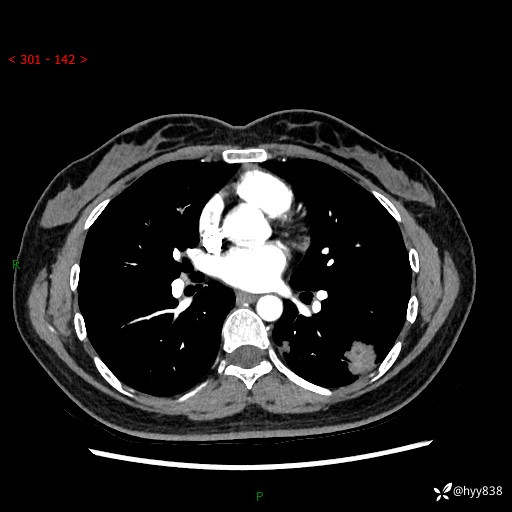

【患者信息】:36岁/女

【主诉】:左侧下胸部阵发性疼痛2周,乏力1周

【现病史及既往史】:患者自诉2周前饮酒后出现左侧下胸部阵发性疼痛,不随呼吸改变,无咳嗽咳痰、头晕头痛、咳血、呼吸困难等不适,于当地第一人民医院查胸部CT提示肺部感染,随后前往我院门诊给予抗感染(左氧氟沙星)治疗1周,自诉胸痛较前好转,感乏力、头晕,偶尔干咳,无咳痰,无发热、畏寒、胸闷、咯血、四肢酸痛、腹泻、腹痛等不适,门诊复查胸部CT提示:左肺下叶感染,病灶较前增加增大,遂以“肺部感染”收入我科。 起病以来,患者精神、饮食、睡眠可,大小便正常,体力体重无明显变化。

【检查】:胸部CT增强(外院平扫)